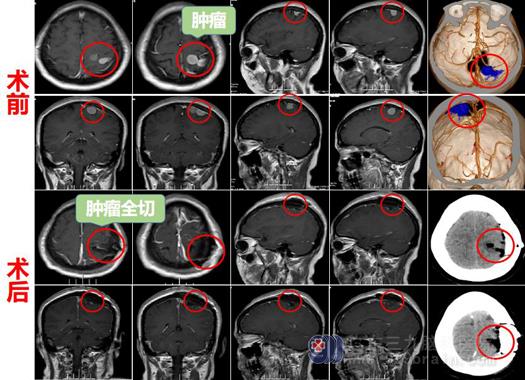

这一检查的结果对于平时能吃能喝的何阿姨来说不亚于晴天霹雳,后经朋友介绍来到广东三九脑科医院神经外十科就诊,入院后查头部核磁共振,检查提示“左侧顶部占位性病变,病灶呈“葫芦样”改变并可见相连,整体范围约28×13×12mm,考虑脑膜瘤”。

经神经外十科欧阳辉教授阅片后介绍道:“何女士的肿瘤在左侧顶部,位于功能区,常规手术会影响手脚活动,为了保障术后功能,采用唤醒手术方式”。

手术后何阿姨恢复可,无功能障碍,术后病理提示“脑膜皮细胞型脑膜瘤,WHO I级”。